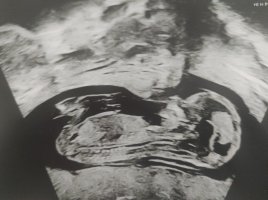

Noissa alemmissa ei näy mitään, mutta kyllä mä nyt sanoisin että poika. Nub on selkeä kyllä, mutta mua jännittää arvioida koska en tiedä jatkuuko se vielä tosta vai oisko koko nub nyt sit tossa kuvassa. 😁